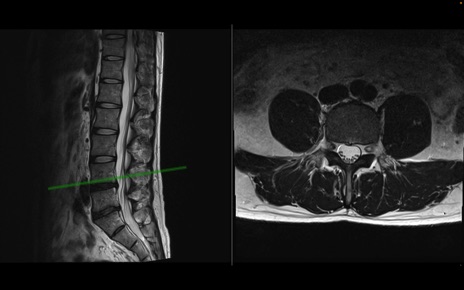

【整形】TIPS症例1 腰椎MRI 横断像と矢状断像

【症例】40歳代男性

【主訴】左臀部〜大腿後面痛み

【現病歴】2週間前から腰痛あり。2日前に夜中にくしゃみをした際に激痛が出現。疼痛強いため来院。

【身体所見】左臀部〜大腿後面、下腿後面のしびれ。SLR -/+ 30度、うつ伏せ困難、筋力低下なし。

異常所見と診断は?